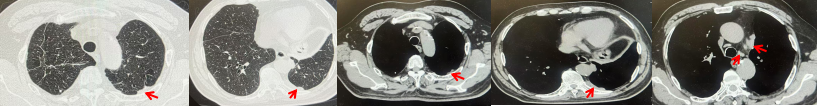

2024.09.12复查胸部CT示左侧胸膜结节,大者约为27mmx13mm,考虑转移可能性大,纵隔淋巴结增大,恶性?(如图6)。患者行胸膜穿刺活检取病理,结果示(胸膜)结合免疫组化,支持鳞状细胞癌,PD-L1(克隆号28-8)TPS约20%。分期为rT0N2bM1a IVA期,DFS为10个月。2024.09.24起行替雷利珠单抗联合紫杉醇+卡铂方案治疗4周期,复查胸CT评效SD(如图7)。后患者因脑梗塞停止治疗,于综合医院就诊,后未返院复查及治疗。

图5:患者手术前(2023.11)胸部CT肺窗及纵隔窗

图6:患者胸膜及纵隔转移(2024.09)胸部CT肺窗及纵隔窗

图7:替雷利珠单抗联合白蛋白紫杉醇+卡铂治疗4周期后(2024.12)胸部CT肺窗及纵隔窗